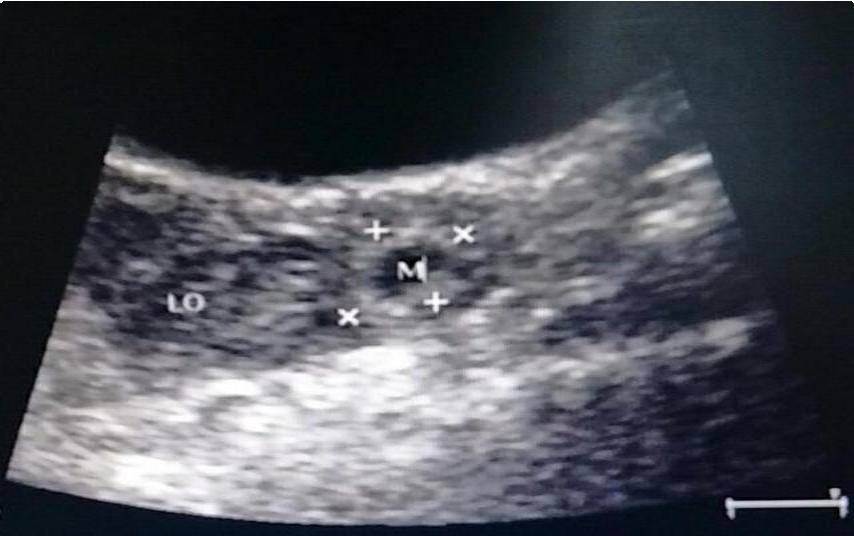

残角子宫妊娠2个月大小

M代表输卵管妊娠囊,LO代表左侧卵巢